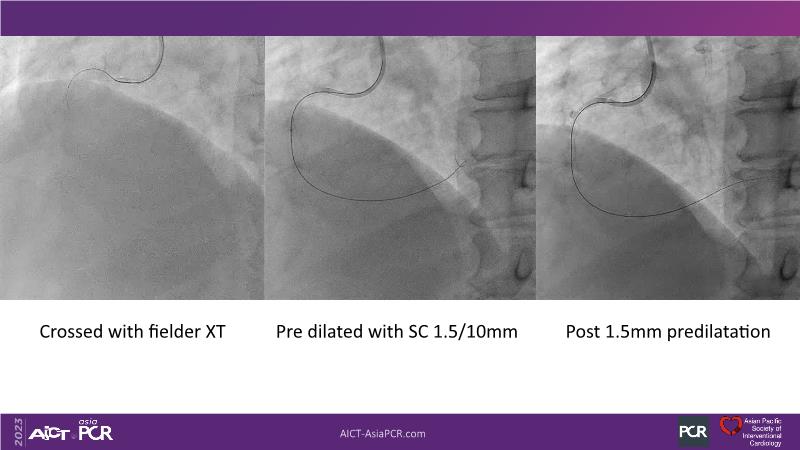

Leave nothing behind: DCB-only PCI strategy - How DCB evidence has changed today's practice?

This session offers an opportunity to stay informed about the recent developments in the International DCB Consensus Group, gain insights into the latest clinical data and real-world experiences related to drug-coated balloon (DCB)-only PCI, understand the safety aspects of DCB in managing complex PCI cases, and participate in an interactive discussion with experts.